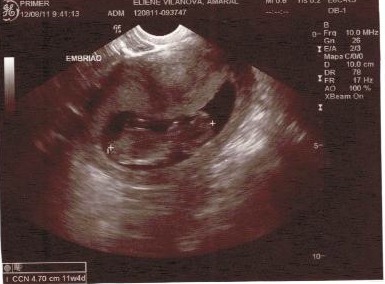

Bem, por aqui essa semana vai ser assim, bagunça, sujeira, mas tudo por uma boa causa. Aaos poucos vou mostando pra vocês, não é nada de capa de revista e muito menos o último grito da decoração de e interiores, apenas um cantinho onde circular muito amor sendo renovado pra receber o dono ou dona, ainda não sei o sexo do baby, essa crianaça não mostra de jeito nenhum.